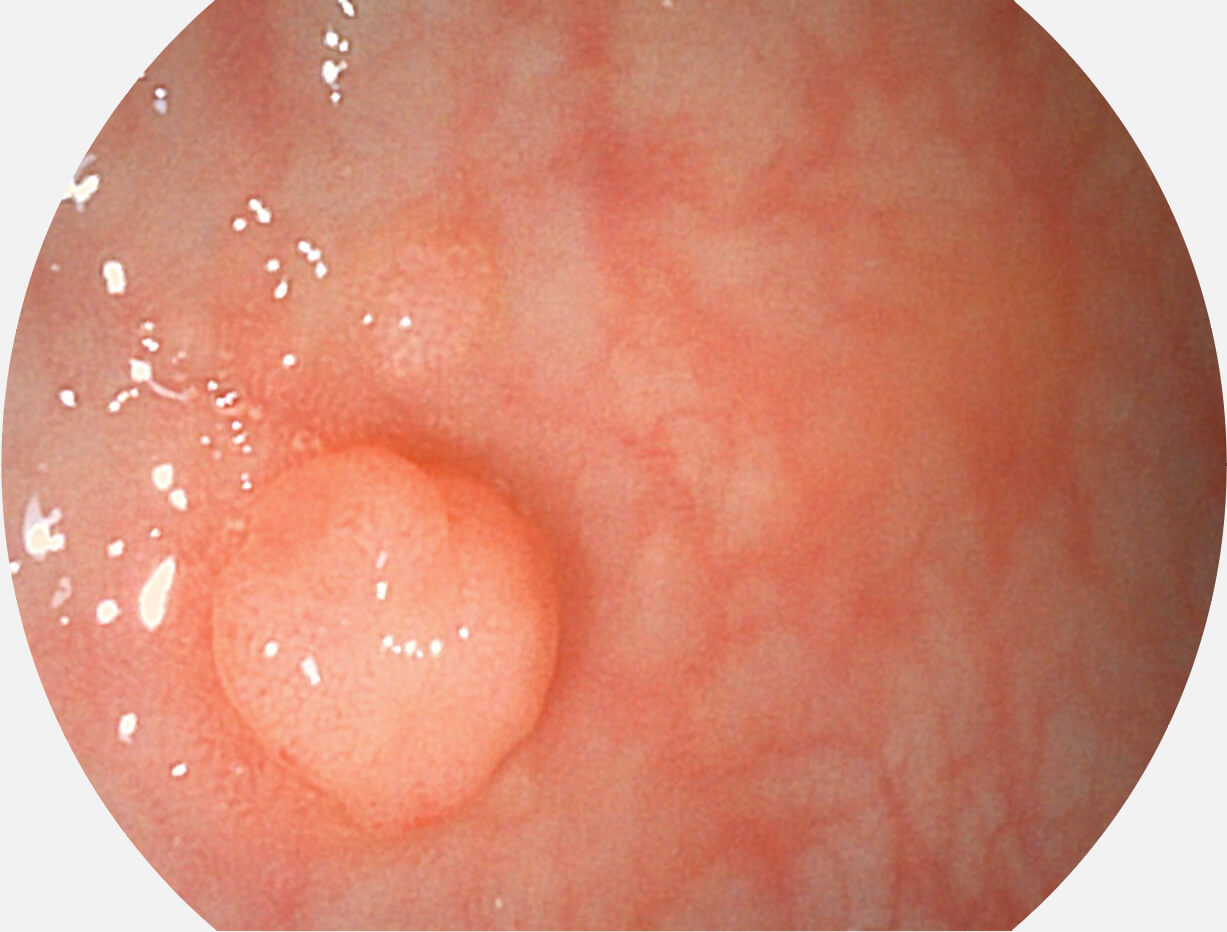

强调浅层黏膜结构的同时,保证照明亮度和提升浅层微血管与中层血管颜色对比度,病变边界更清晰。

VIST图像